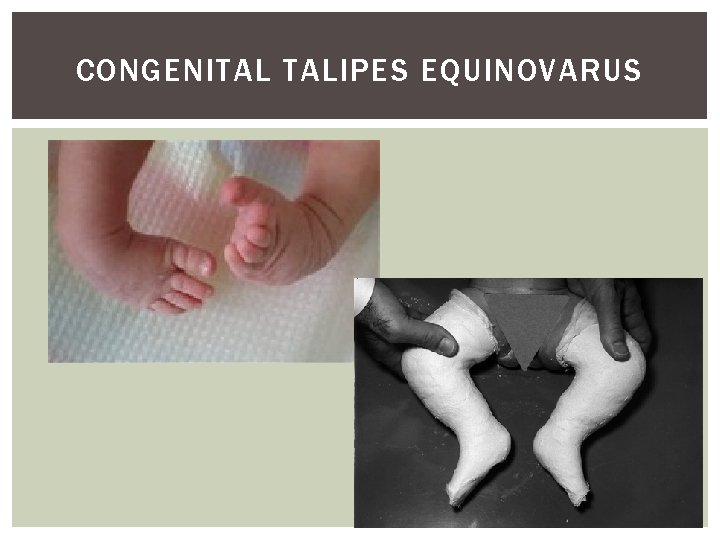

CONGENITAL TALIPES EQUINOVARUS